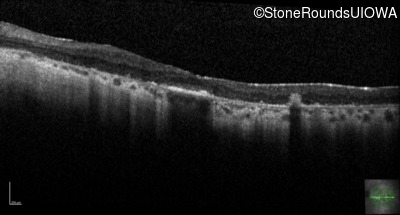

Visit at age: 35 years

Optical Coherence Tomography - Left - 20/70

Exemplar / OCT Stack